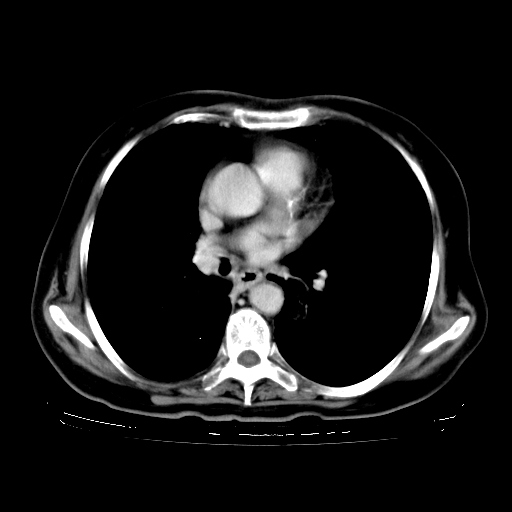

2.胸主动脉夹层。

支持,首先一元论解释。胸主动脉部分层面环形低密度,中心强化。环形影不强化。不象真假腔的改变。我考虑动脉炎,不太支持夹层动脉瘤-和大家的观点不一致,希望楼主让患者再做个心血管的彩超吧。

继发型肺结核,右下肺支气管内膜结核.右侧少量胸腔积液.主动脉夹层.

支气管内膜结核肺内播散.右侧少量胸腔积液.主动脉夹层.